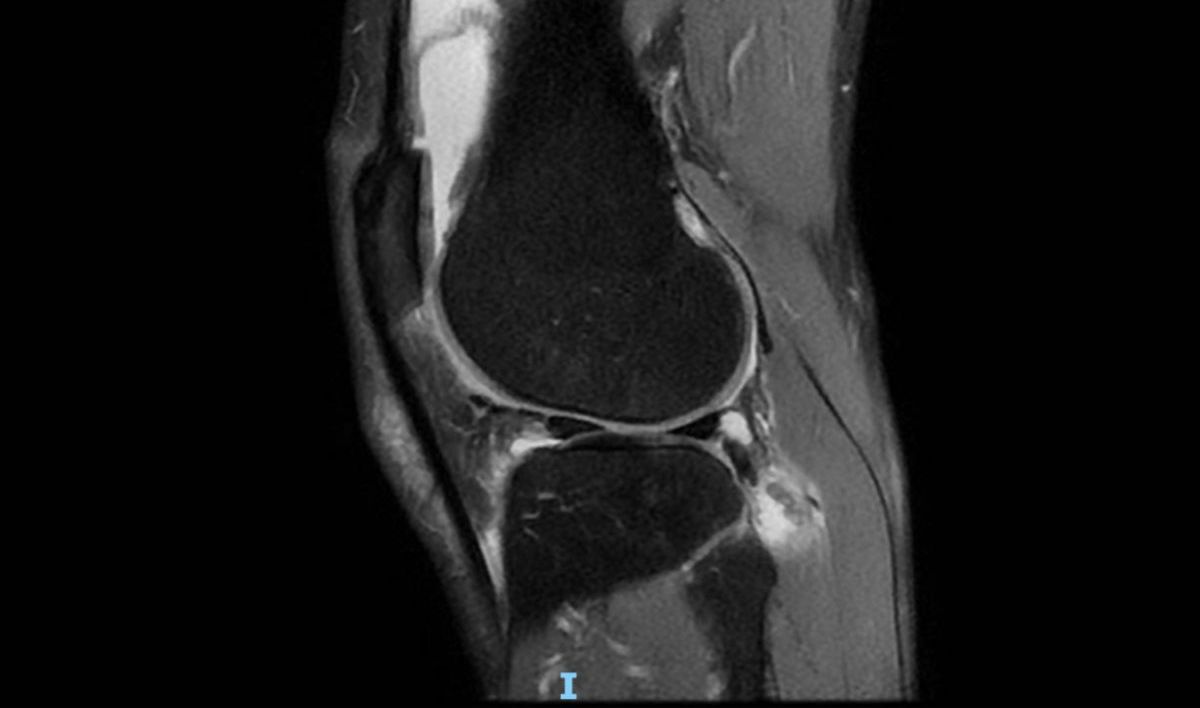

El diagnóstico del Dr. Luis Valenzuela de la Clínica Meds en Santiago de Chile que detuvo mis 3 años y 21 días corriendo todos los días, fue contundente: “Tienes evidentemente una artrosis femorotibial interna, con rotura degenerativa de menisco interno. También lesiones condrales en la rótula. Hay edema óseo del cóndilo femoral interno y de platillo tibial interno por el desgaste articular y la sobrecarga”.

En palabras simples, los resultados de la prueba de resonancia magnética (MRI por sus siglas en inglés), mostraron cuán gravemente arruiné mi rodilla izquierda, principalmente por un grave caso de terquedad, ubicado muy cerca de la línea de la estupidez.

Obviamente, no hice caso hasta que el pasado 21 de agosto de 2023, al finalizar mi viaje anual de esquí a Chile, por fin decidí hacerme revisar la rodilla izquierda por el Dr. Valenzuela, quien tras un rápido examen visual y de tacto, determinó de inmediato que era necesaria una resonancia magnética.